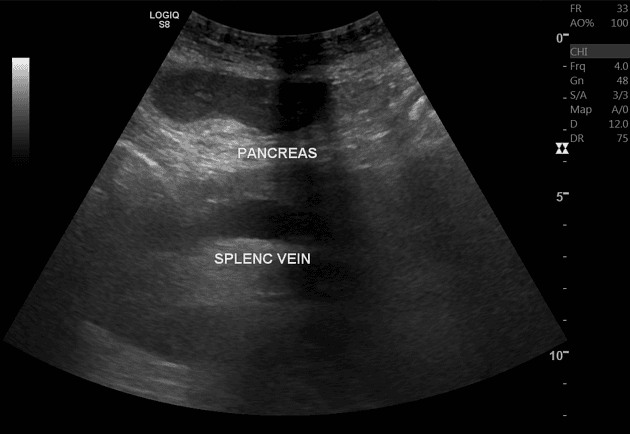

- Tụy to.

- Cả tụy và mô mỡ quanh tụy vùng sau phúc mạc đều tăng tín hiệu, gợi ý phù.

Do chẩn đoán xơ gan, bệnh nhân được đưa vào chương trình theo dõi ung thư tế bào gan (HCC) định kỳ 6 tháng/lần. Tuy nhiên, gan quá không đồng nhất về cấu trúc mô đệm nên siêu âm (US) không đủ chất lượng để đánh giá hình ảnh, do đó bệnh nhân được chuyển sang theo dõi bằng cộng hưởng từ (MRI) mỗi 6 tháng.

Trong lần khám này, phát hiện phù tụy mới xuất hiện. Bệnh nhân lúc đó trong tình trạng ổn, ở nhà, không đau bụng. Do lo ngại rằng phù tụy có thể là dấu hiệu của viêm tụy cấp, nồng độ amylase và lipase trong huyết thanh đã được đo – cả hai đều trong giới hạn bình thường.

Ở bệnh nhân này, chỉ có hình ảnh học gợi ý viêm tụy cấp, trong khi không có triệu chứng lâm sàng và men tụy bình thường, do đó không chẩn đoán viêm tụy cấp.